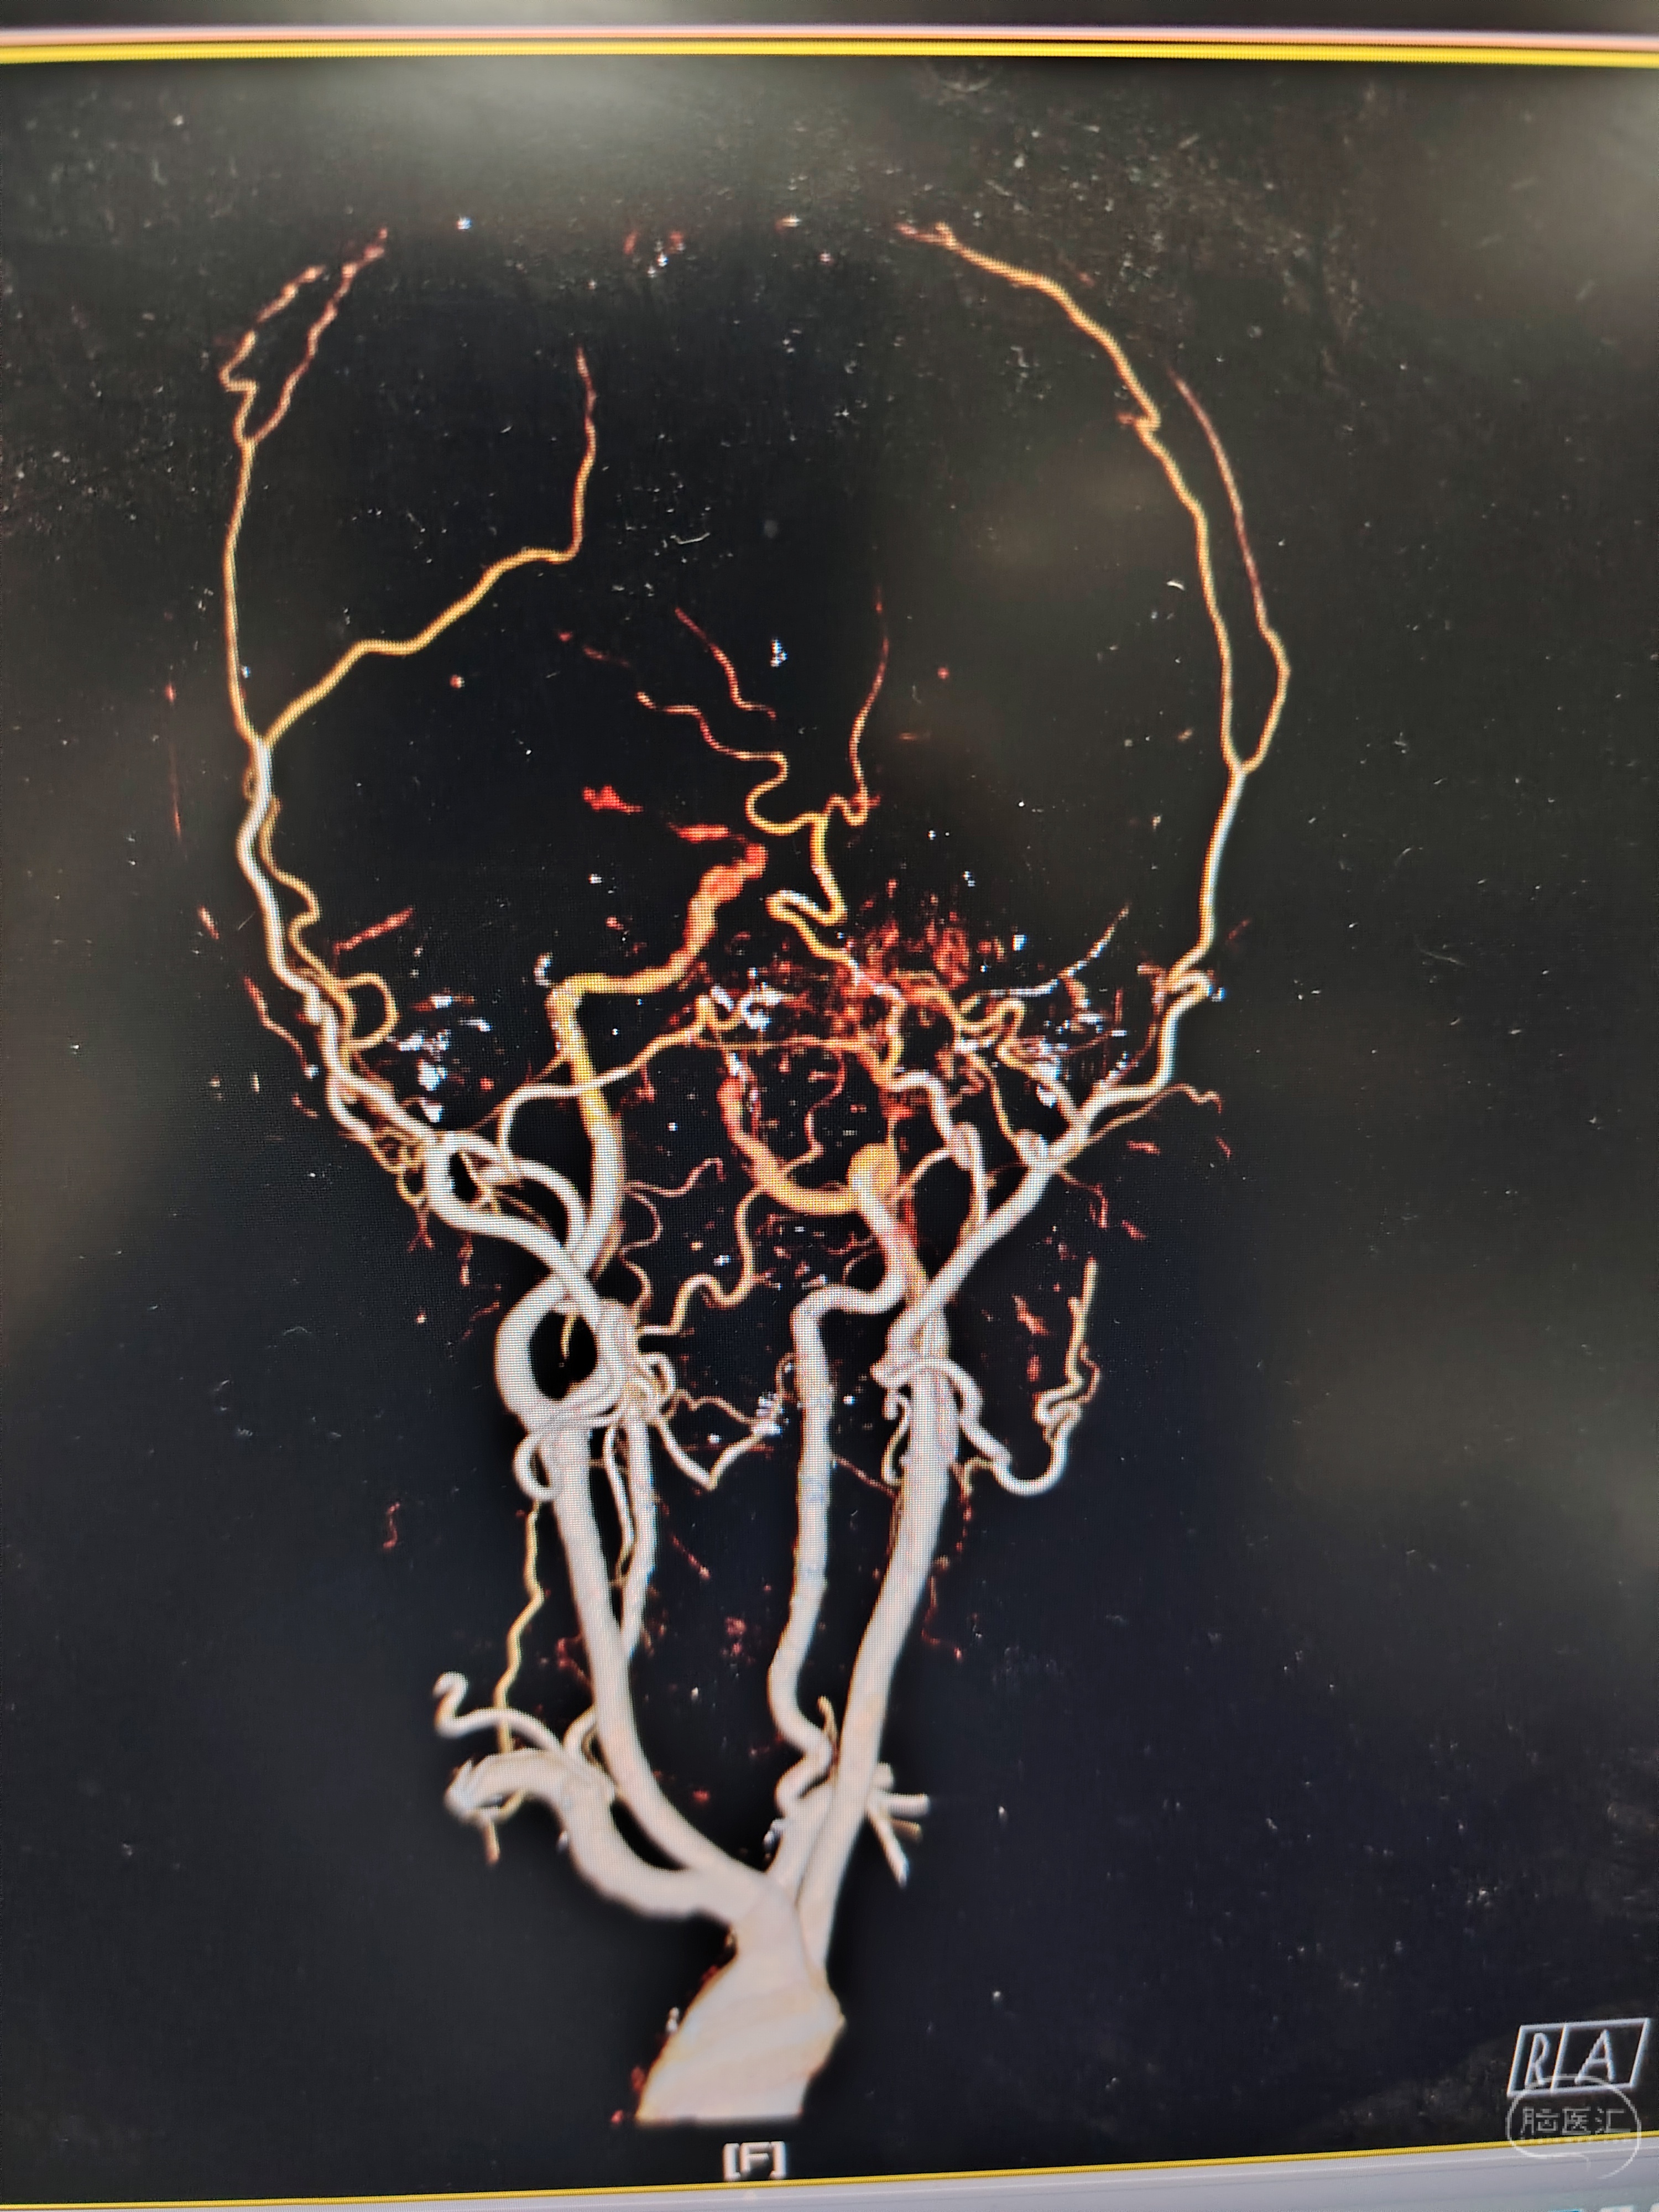

发病前MRA示颅内多发动脉瘤。

急症CTA颅内血管不显影。